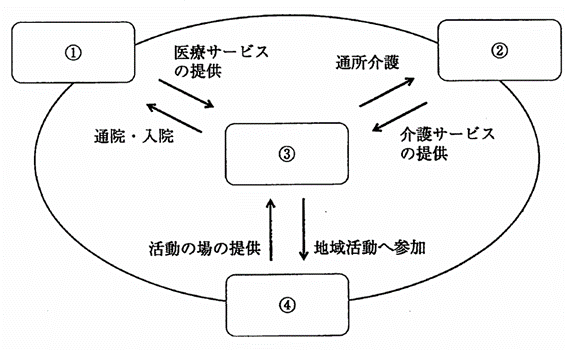

地域包括ケアシステムの概念を図に示す。「住まい」はどれか。1つ選べ。

a. ①

b. ②

c. ③

d. ④

解答を見る

c